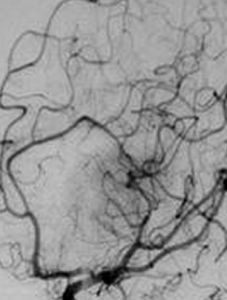

老分類中稱蔓狀血管瘤或葡萄狀血管瘤。是一種紆迴彎曲、極不規則而有搏動性的血管畸形。主要是由血管壁顯著擴張的動脈與靜脈直接吻合而成,故亦有人稱為先天性動靜脈畸形(congenital arteriovenous malformation)。動靜脈畸形多見於成年人,幼兒少見。常發生於顳淺動脈所在的顳部或頭皮下組織中。病損高起呈念珠狀,表面溫度較正常皮膚為高。病員可能自己感覺到搏動;捫診有震顫感,聽診有吹風樣雜音。若將供血的動脈全部壓閉,則病損區的搏動和雜音消失。腫瘤可侵蝕基底的骨質,也可突入皮膚,使其變薄,甚至壞死出血。

表淺血管瘤或脈管畸形的診斷並不困難。位置較深的血管瘤或脈管畸形應行體位移動試驗和靠穿刺來確定。對動靜脈畸形以及深層組織內的靜脈畸形、大囊性淋巴管畸形等,為了確定其部位、大小、範圍及其吻合支的情況,可以採用超聲、動脈造影、瘤腔造影或磁共振血管成象(MRI或MRA)來協助診斷(方法詳見《口腔頜面X線診斷學》及有關參考書籍),並為治療作參考。從細胞生物學分類的觀點來看,成人的脈管病損基本上都應屬脈管畸形。嬰幼兒期的動靜脈畸形、微靜脈畸形、淋巴管畸形亦均屬脈管畸形。高出皮膚的所謂楊梅樣血管瘤自發性消退的可能性較大,一般應屬血管瘤。嬰幼兒期特別是一出生即發現的靜脈畸形,其所屬類型如何判斷尚需進一步研究。有研究指出:血清中血管內皮生長因子(VEGF)和雌激素受體等在血管瘤明顯升高;而細胞凋亡基因bcl-2在脈管畸形中呈高表達,但僅供參考。

動靜脈畸形,主要採用手術治療。手術時應先結紮切斷與腫瘤交通的動脈,爾後再切除病變。有時因病變廣泛,手術時需作一側或雙側頸外動脈結紮,以減少出血。近年來,由於介入放射學(interventional radiology)的發展可以套用經導管動脈栓塞技術(transcather arterial embolization, TAE, TCAE),以控制和減少術中出血。其止血效果遠較頸外動脈結紮為好;因為除動脈主幹外,動脈的各級分支,直至終末支均可得到栓塞,沒有末梢血管壓力驟降、管腔開放、反而形成側支循環之弊。常用的有效而安全的栓塞材料是明膠海綿。應當指出:曾有人試圖單獨套用頸外動脈結紮術以治療動靜脈畸形,經驗和實驗研究證明,不但無效,而且可以促進非正規的側支循環形成,反給後期進一步治療帶來困難和麻煩。套用頸外動脈結紮術治療動靜脈畸形不但在實際上是無效的,而且在理論上也是錯誤的。